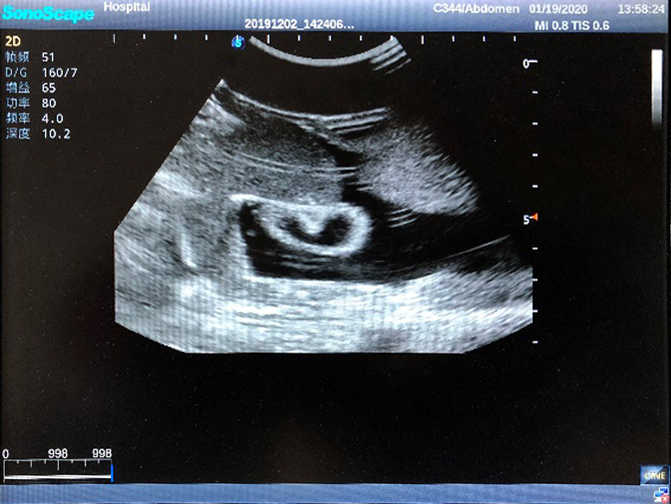

1)  Ideal for trainings like ultrasound-guided abdominocentesis with visible ascites flowing out, ultrasound-guided femoral artery & venous puncture

2)  High quality ultrasound image with clear structures like gallbladder, liver, intestines, arteries and veins etc.

3)  Compatible with all types of clinical ultrasound machines